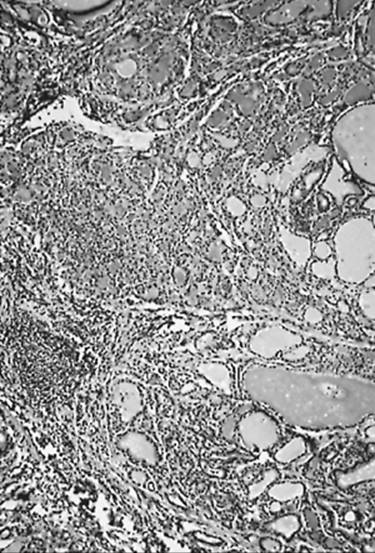

Microscopic examination shows that many follicles are small, the amount of colloid is decreased, and infiltrates of lymphocytes, plasma cells, and macrophages are extensive (Fig. 21.2) (70,71). Lymphoid follicular centers are numerous, and their antibody-producing B-cells are polyclonal; those containing IgG are the most numerous (59,60,61,68,72). T-cells are most frequent among the epithelial cells and in the interstitial tissue away from lymphoid follicles. In flammatory giant cells may be scattered through the damaged follicles; their presence should not lead the pathologist to mistake autoimmune thyroiditis for de Quervain's thyroiditis (71). The amount of connective tissue in the gland often increases. Some follicular cells appear atrophic or damaged; many are hyperplastic or metaplastic (oncocytic or Hürthle cells; squamous metaplasia) (73,74). The solid-cell nests have been suggested as the origin of the latter (21,74). Possibly related rare cystic lesions have also been noted (38,40,75,76).

FIGURE 21.2. Autoimmune thyroiditis. Lymphoid follicles are conspicuous. Only a few colloid-filled thyroid follicles remain; most of these follicles are small and were formed by hyperplastic and metaplastic cells.